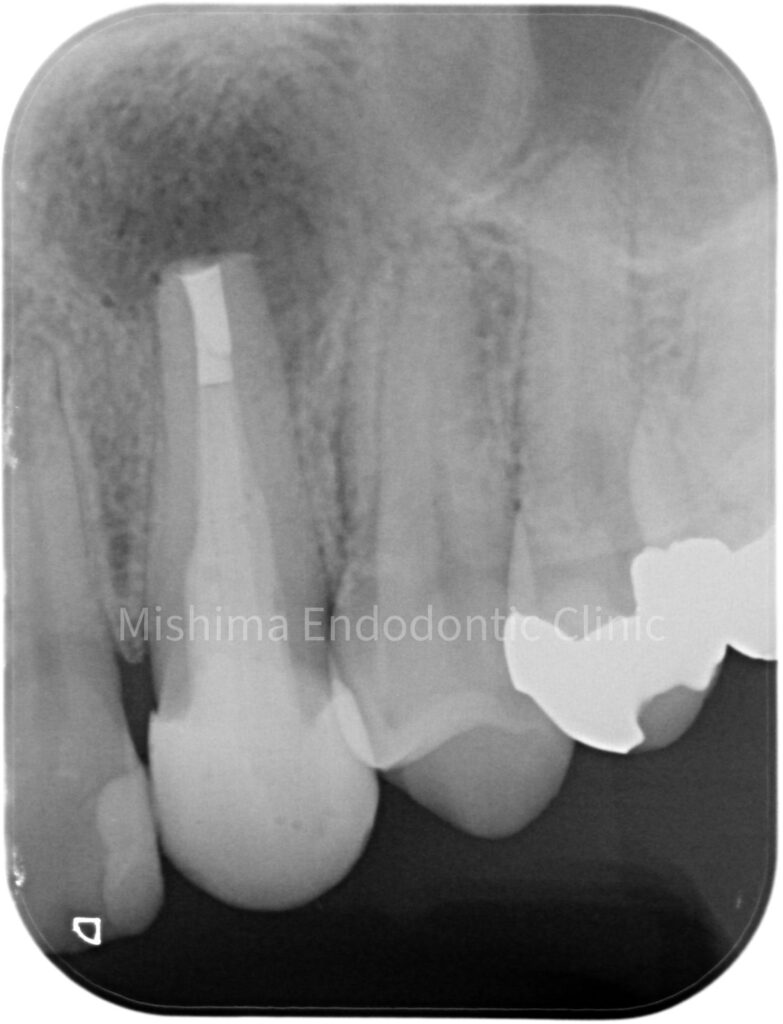

After

| 治療内容 | 23が既に根管治療が介入され仮封の状態で、サイナストラクト、自発痛を認めた。 根管治療を行うも症状の改善認めず、歯根端切除術へ移行。 |

歯根端切除術 直後

術後 2年6ヶ月

CBCT 術前術後